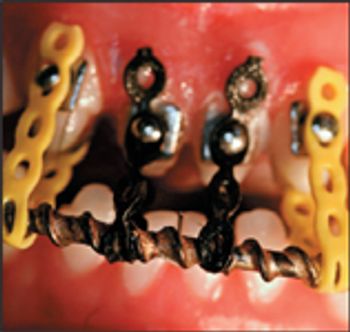

Symphyseal fracture repair in cats has been performed traditionally by placing a ligature wire circumferentially around the anterior mandible and securing the right and left mandibular bodies by tightening the ligature wire. This method is not only invasive, but often results in an unstable symphyseal reduction because of the faculty of ligature wire to stretch over time.